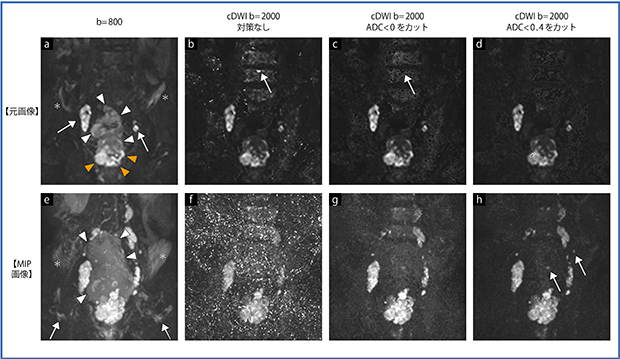

図3 高輝度ノイズと低ADC値カットオフの効果

80歳代,男性,前立腺癌,多発リンパ節転移症例。以下,単位は省略して説明。

a:b=800元画像において,▶で示す前立腺癌を認める。また,腸骨リンパ節転移(→)を認める。原発巣と転移巣以外に,▶で示す膀胱(変形している)や腹水(*)が認められる。

b:b=2000のcDWIにおいては,高輝度ピクセルが無数に出現している。ADC<0となっているためにこのような結果となる。↑で示す部分は特に問題で,骨転移と区別がつかない。

c:ADC<0をカットした画像では,この高輝度偽病変が取り除かれている。

d:ADC<0.4をカットした画像では,そのほかに椎体にも多数の欠損点が現れる。ADCが正の領域に踏み込むこの演算がすべて正しいとは言えないが,ノイズの存在により不当にADCが低く見積もられている可能性がある領域である。

e:b=800 MIP画像では,膀胱(◀)や腹水(→),あるいは腎臓が背景信号として表示されている。こういった構造物に重なった,あまり信号強度が高くない病変は,MIP画像に表示されないことになる。fのb=2000のcDWIでは,元画像で認められた高輝度点が天の川のように認められ,内部の病変を見難くしている。gのADC<0をカット,hのADC<0.4をカットしたMIP画像では高輝度ピクセルとともに背景がよく抑制され,↑で示すような淡い高信号を示す転移リンパ節も明瞭になっている。